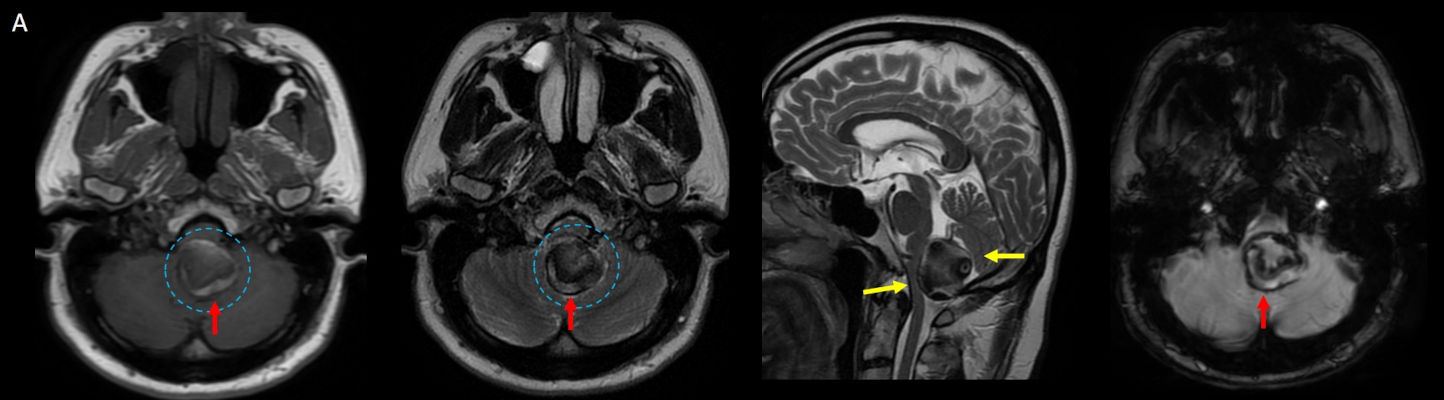

- A. Posterior fossada, T2A, T1A görüntü ve SWAN sekanslarda, 3.5 cm boyutta, düzgün sınırlı, T1A hiperintens, T2A hipointens heterojen iç yapıda kitlesel lezyon izleniyor (çember). Lezyonun serebellum ve kraniyoservikal bileşkeye bası etkisi mevcuttur (ok). Lezyon periferinde T1A, T2A ve SWAN görüntülerde hiperintens tubuler yapı bulunmaktadır (ok). Bu yapı intralezyonel “yılanvari eksantrik vasküler’’ yapıdır.

- MR

- Kısmen tromboze olmuş dev serebral anevrizma, kan ürünlerinin değişken yaşına bağlı olarak MRG’de heterojen bir sinyale sahiptir.

- T1 kısmen tromboze anevrizmada genellikle hiperintens odaklarla heterojen

- T2 kısmen tromboze anevrizmada genellikle hipointens odaklarla heterojen, serpantin anevrizma içi damar kanalında akım boşlukları, bitişik parankimde vazojenik ödem görülebilir.

- T2 ve SWAN genellikle santral-çevresel duyarlılık artefaktları görülür.

- MRA serpantin anevrizma içi damar kanalı iyi gösterir.